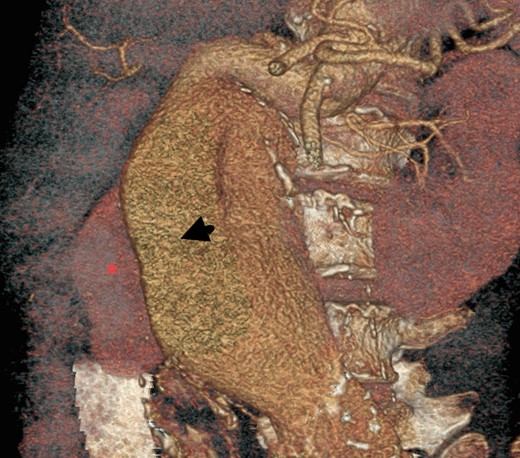

On arrival at our hospital, she was hemodynamically stable, with all vital signs within the normal range. Abdominal examination revealed a pulsating mass in the center of the abdomen. A computed tomography (CT) angiogram of aorta was performed for further evaluation that showed ectatic aorta from arch to the diaphragm. There was an 8.7-cm infra-abdominal AAA with extension into both common iliac arteries. The aneurysm neck was tortuous with an acute angle making endovascular repair challenging (Figs 1–4).

Three-dimensional construction of CT aortogram showing displaced and compressed IVC (asterisk) due to large AAA (arrow head).